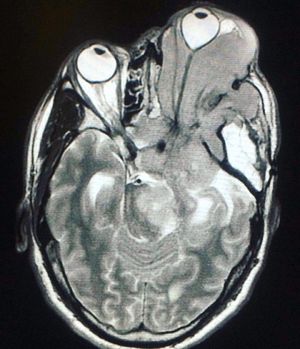

This patient was admitted to the hospital with the main complaint of double vision (diplopia). An MRI was done and demonstrated a mass, seen on the image above, diagnosed as an extracranial meningioma. Extracranial or extradural meningiomas are rare location-specific type of meningiomas that arise outside the dural covering of the brain and spinal cord, the majority being a secondary location of a primary intracranial tumour. They most often occurring in the head and neck region, specifically in the sinonasal tract, temporal bone and ear, and in the scalp.Symptoms vary according to the region where the mass appears (that explains the double vision in this patient). Prognosis of this tumour is generally excellent. Surgical excision is the treatment of choice, with no need for further treatment; nevertheless, differential diagnosis must consider other more common tumours of the head and neck and be based on histopathologic examination.